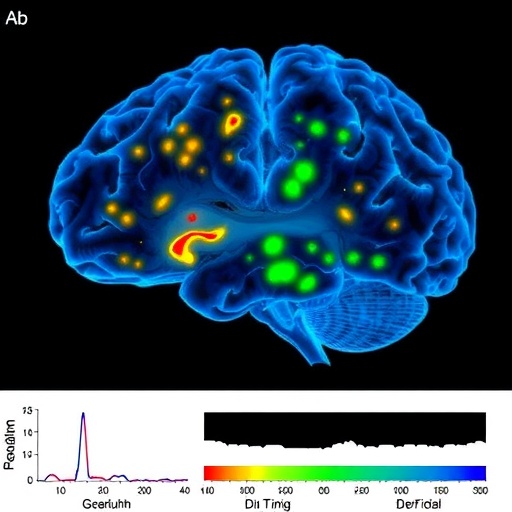

Brain Maintenance Biomarkers in Aging and Neurodegeneration

Brain Imaging Study Reveals Ethnoracial Variations in Dementia Risk and Progression